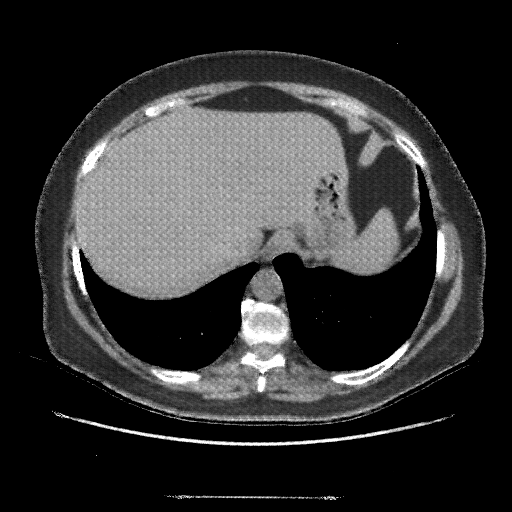

Reconstructed NATIVE CT scan (cycle consistency)

No window - Raw intensity values

Lung window (WL -600, WW 1500 β†’ Low βˆ’1350, High +150)